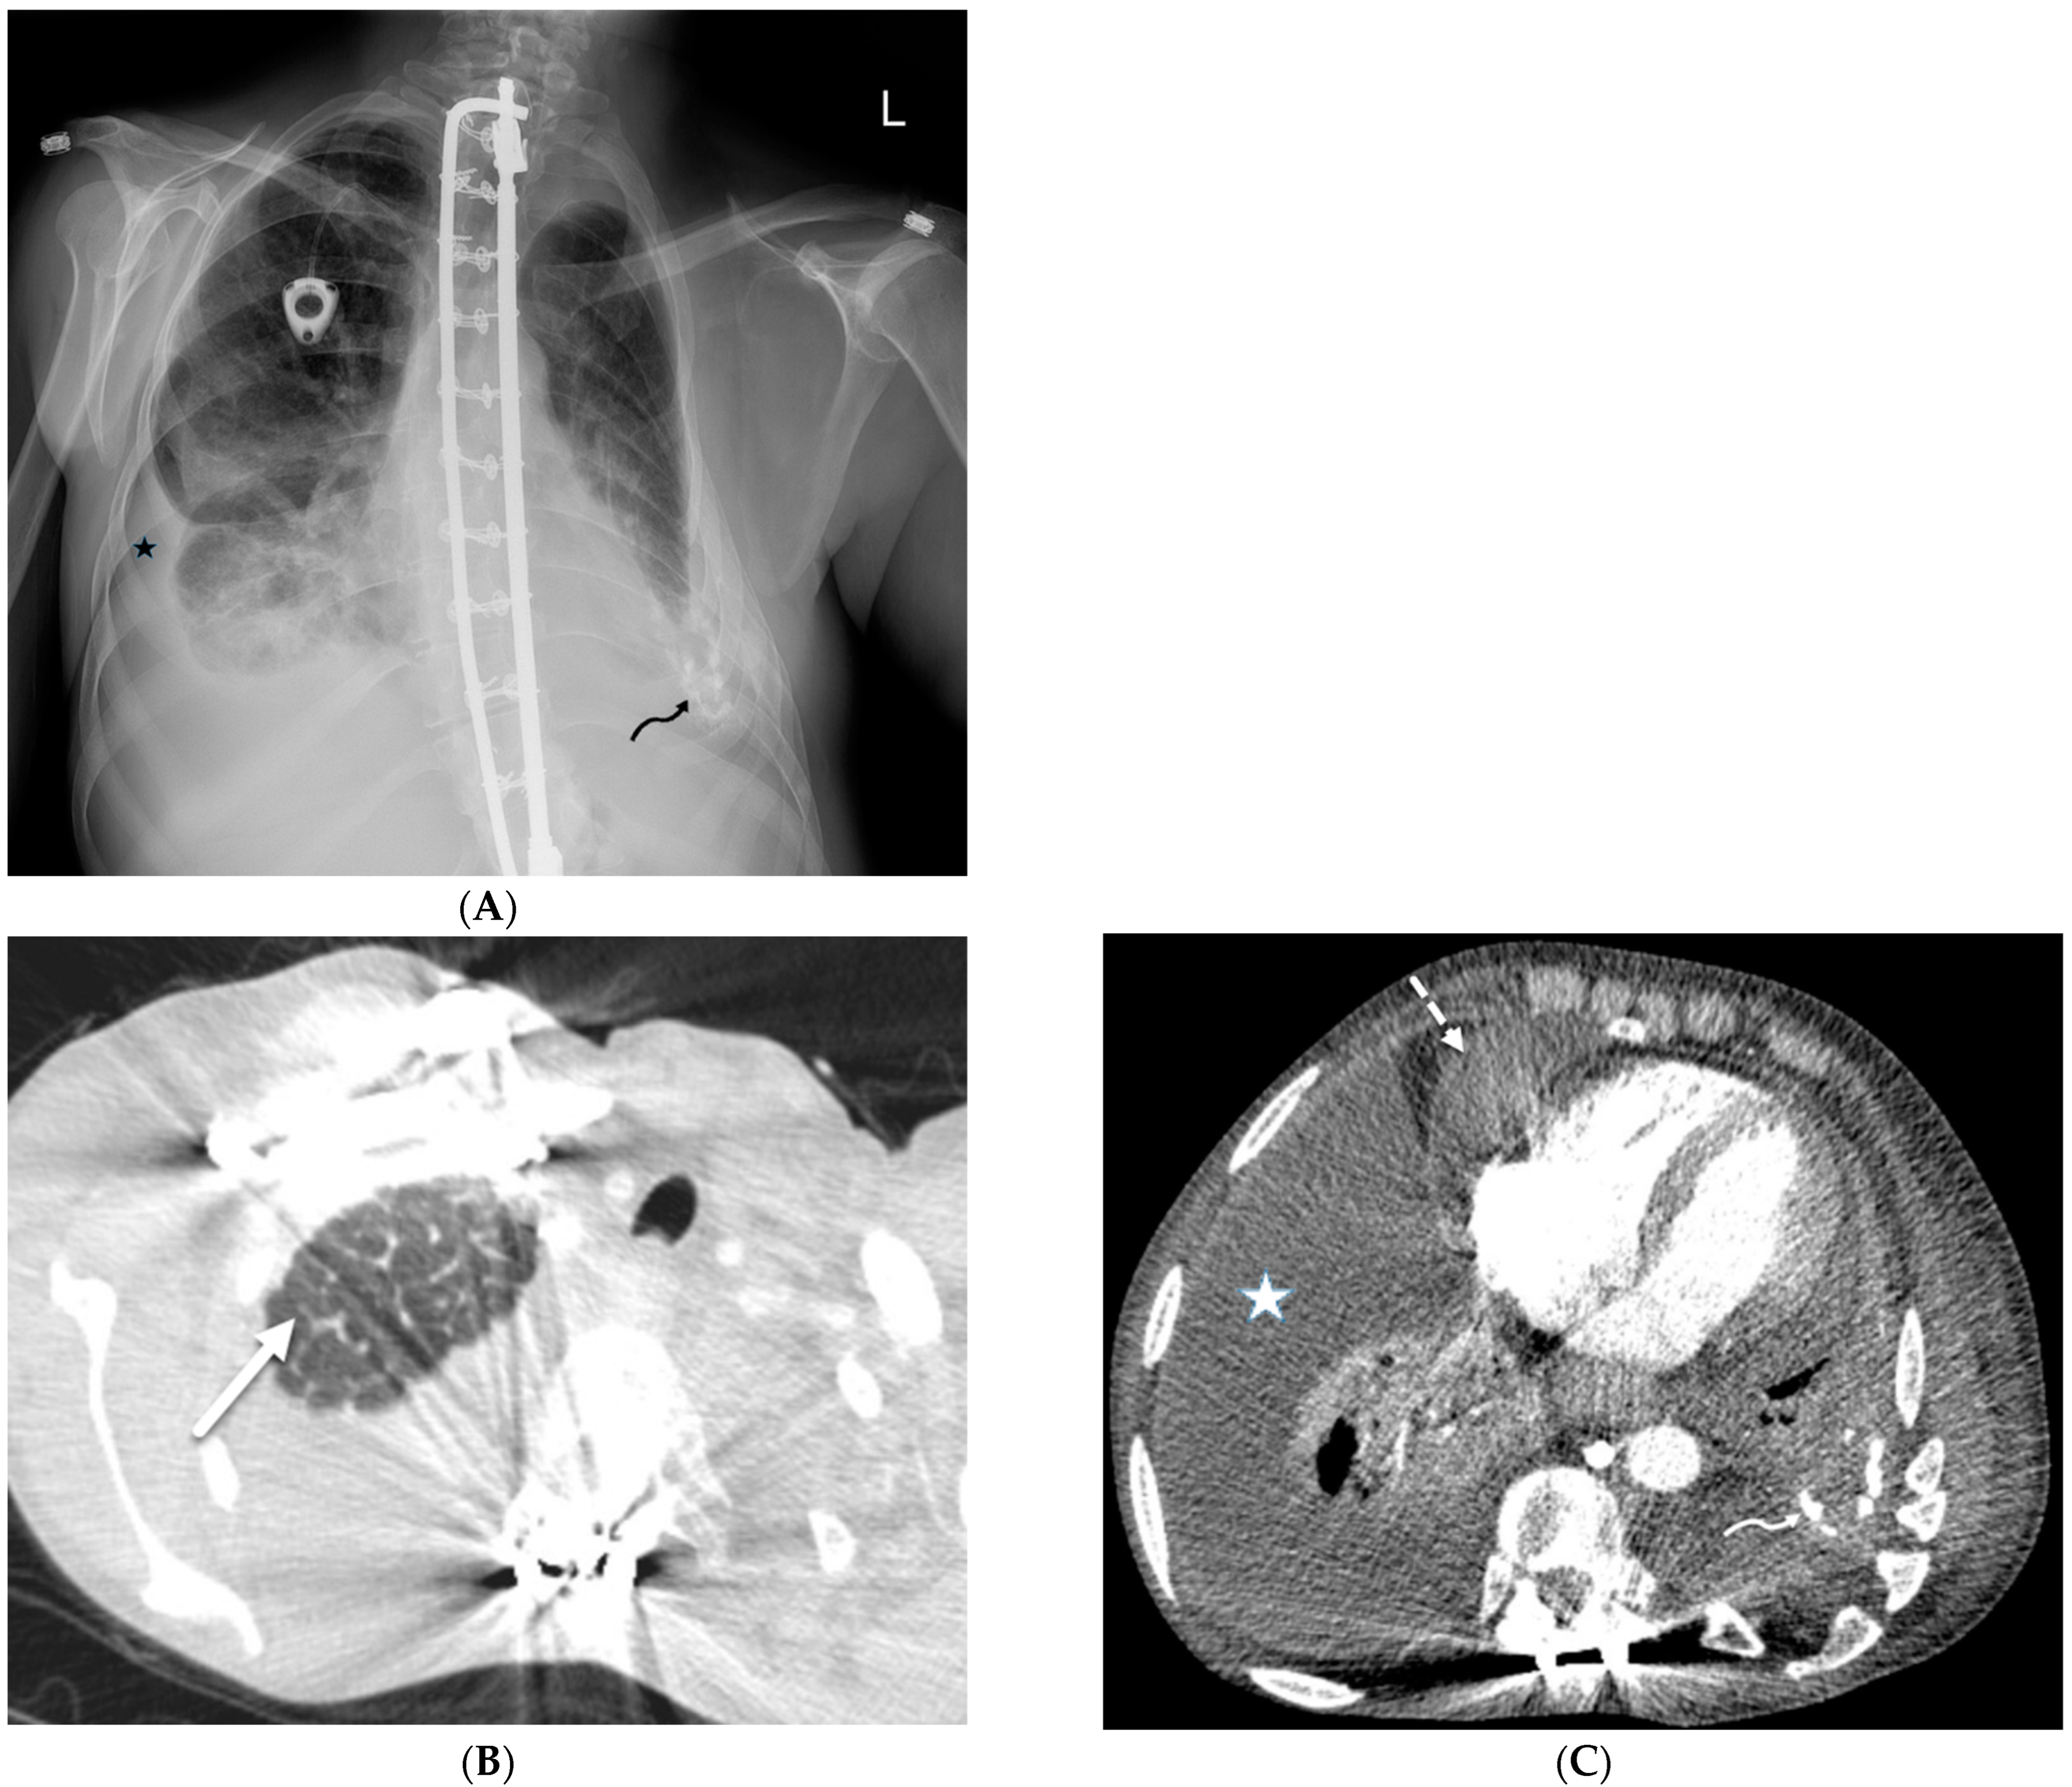

| Silicone embolization | History of illegal cosmetic injection of liquid silicone | Multiple subcutaneous soft tissue attenuation nodules, sometimes with peripheral calcification or surrounding fat stranding |